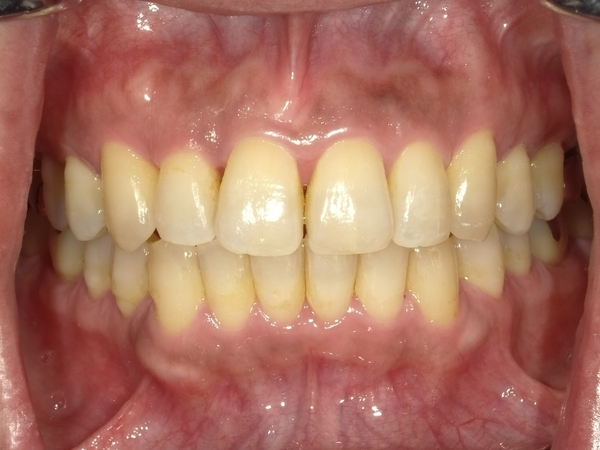

ガタガタとした歯並びや八重歯(叢生)CASE71